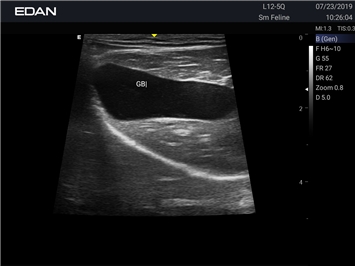

Ветеринарный ультразвук одним нажатием. Система Acclarix AX2 VET разработана с целью обеспечить бескомпромиссную производительность по доступной цене. Наличие уникальных двойных аккумуляторов в легком корпусе массой 4,5 кг из магниевого сплава позволяет системе Acclarix AX2 VET удовлетворять все потребности ветеринарных исследований, сохранив низкую стоимость.

EDAN Acclarix AX2 VET представляет собой специализированную ветеринарную ультразвуковую систему, сочетающую высокую производительность с доступной ценой. Благодаря продуманной конструкции и передовым технологиям, система обеспечивает качественную диагностику животных различных видов.

• Высокое разрешение для детальной диагностики

• Улучшенная визуализация глубоко расположенных органов